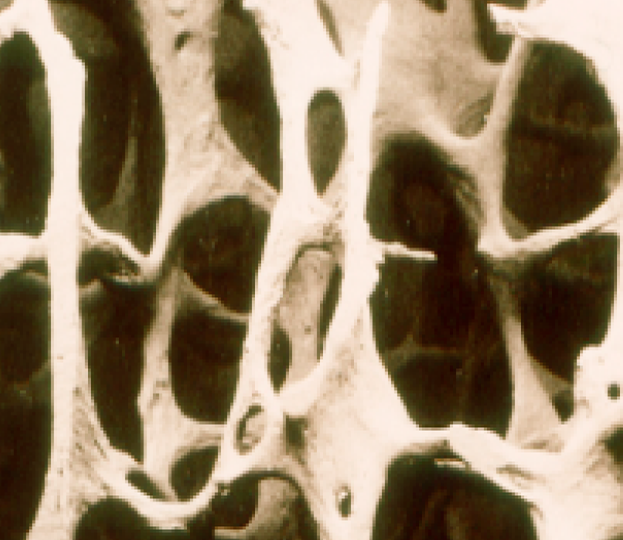

UNHEALTHY BONE

Many people think that their bones are just like timbers or steel which supports the structure of a house. They are not. Bones absolutely support us, but bones are an ever-changing, living and dynamic organ. More below.